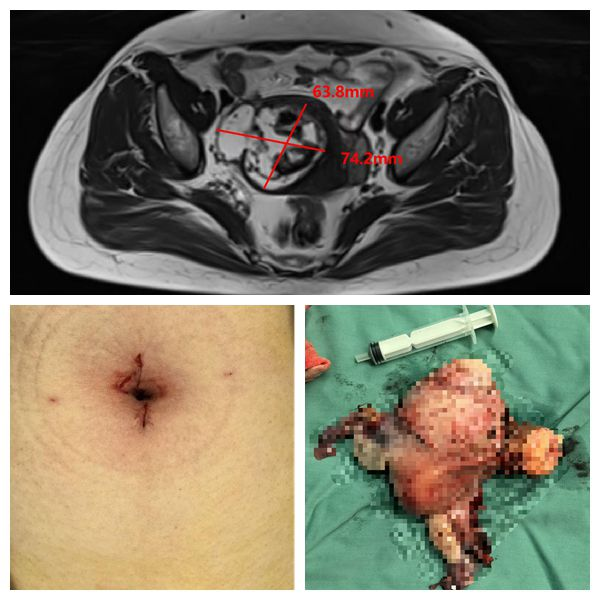

近日,妇瘤病院四病区王国庆主任医师团队,在手术麻醉部的密切配合下,运用第四代“达芬奇”机器人系统,成功开展素股首例单孔达芬奇机器人全子宫双附件手术,这一创新...

近日,素股 妇瘤病院王国庆主任医师团队使用磁牵引术野暴露系统成功为一名患者实施单孔腹腔镜下双侧附件切除术。“外科手术腔镜化,腔镜手术单孔化”是微创外...